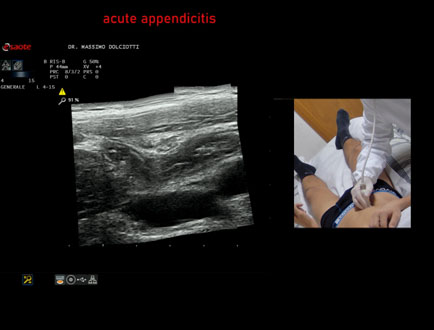

Ecografia del: 13/02/2026

Strumento: Esaote MyLab Eight

Sonda: Lineare Multifrequenza 4-15 MHz

Età Paziente: M 22 anni

Motivazione dell'esame: da un giorno dolori addominali in sede ileo-cecale.

Commento all'esame: le immagini ed il video documentano, in sede ileo-cecale, appendice di spessore aumentato (9 - 10 mm - V.N. inferiore a 6 mm) con incremento della vascolarizzazione. Gli elementi ecografici segnalati orientano per appendicite acuta.

Conclusioni: appendicite acuta (acute appendicitis).

In collaborazione: Dr.ssa Marica Manfredi - Ancona, Dr. Ilir Qose - Ancona

Presentazione: Dr. Massimo Dolciotti - Ancona